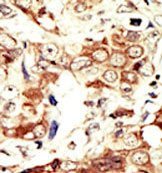

Supportive validation

- Submitted by

- Acris Antibodies GmbH (provider)

- Main image

- Experimental details

- Formalin-fixed and paraffin-embedded human cancer tissue reacted with the primary antibody, which was peroxidase-conjugated to the secondary antibody, followed by AEC staining. This